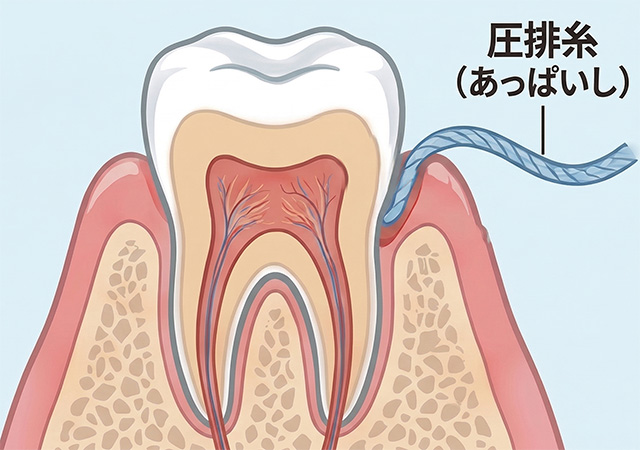

セラミック治療では、かぶせ物の適合精度が見た目や長持ちに大きく影響します。当院では、歯と歯ぐきの境目を一時的にやさしく広げる「歯肉圧排」を行い、細部まで正確に型取りを行います。歯と歯ぐきの境界が明確になることで、段差や隙間の少ないセラミックの製作が可能となり、汚れがたまりにくく、虫歯や歯周病の再発リスクも軽減します。自然で美しく、長く快適に使える仕上がりを目指した大切な工程です。

歯肉圧排による正確な型取り

歯と歯ぐきの境目を正確に記録するため、専用の糸を用いて歯ぐきをやさしく広げる「歯肉圧排」を行います。

この工程を省くと、

といった問題が起こることがあります。

当院では、ミクロン単位の精度で型取りを行うことを徹底しています。

歯肉圧排下での正確な型取り(シリコーン印象)

歯と歯ぐきの境目を正確に記録するため、専用の糸を用いて歯ぐきをやさしく広げる「歯肉圧排」を行います。紫の糸を歯ぐきの中に入れています。

また型取りの際には変形量の少ないシリコーン印象材を用いて行います。※写真は別症例

ここが保険診療の被せものの作製と異なる点の一つです。